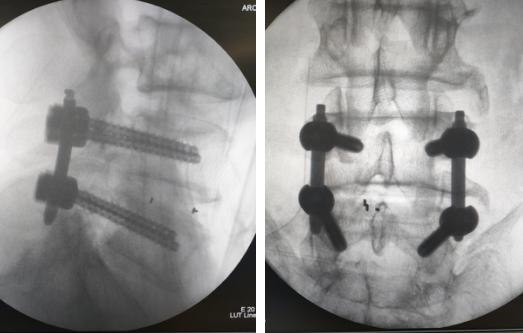

上图:在机器人辅助下,精准置钉

详细的术前准备后,尚军主任张冶副主任医师团队为老人进行了“腰椎后路减压+内固定+融合术”,手术切口仅3厘米,基本不造成患者肌肉软组织损伤,手术时间也大幅缩短。术后老人的腰痛和左腿的痛麻消除,在脊柱病区康复,很快能下地行走。